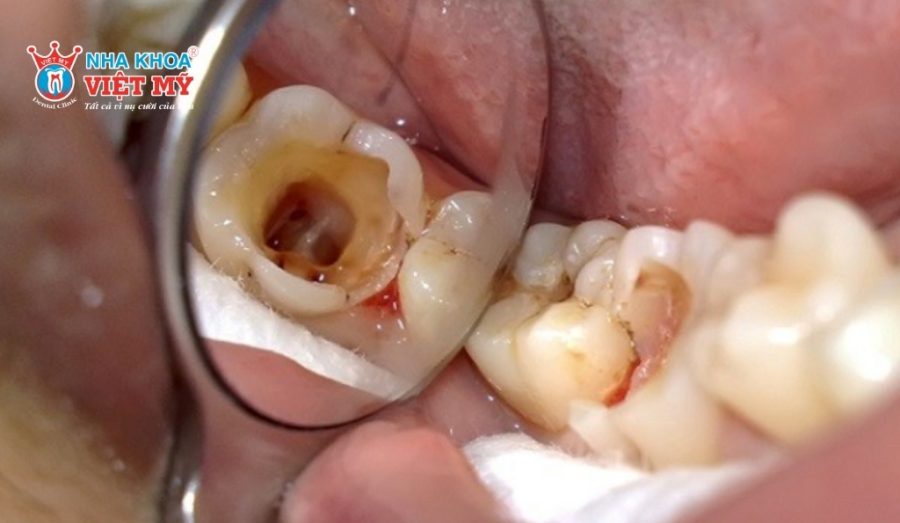

Răng sâu lớn, mô răng bị tổn thương nhiều

Ở người lớn tuổi, răng dễ bị sâu lan rộng do men răng đã yếu. Khi lỗ sâu quá lớn, mô răng bị tổn thương, việc trám răng không còn hiệu quả vì không đủ mô răng khỏe để giữ vật liệu trám. Lúc này, bọc răng sứ sẽ giúp bảo vệ phần răng còn lại, đồng thời phục hồi khả năng ăn nhai một cách ổn định.